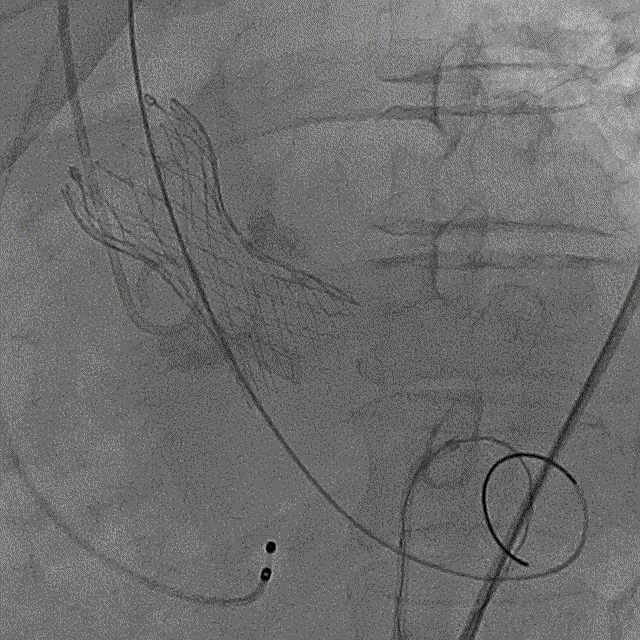

最终造影

主动脉弓剪影,瓣膜植入深度3mm,冠脉显影正常,主动脉弓正常

术后即刻压差从81mmHg下降至23.9mmHg